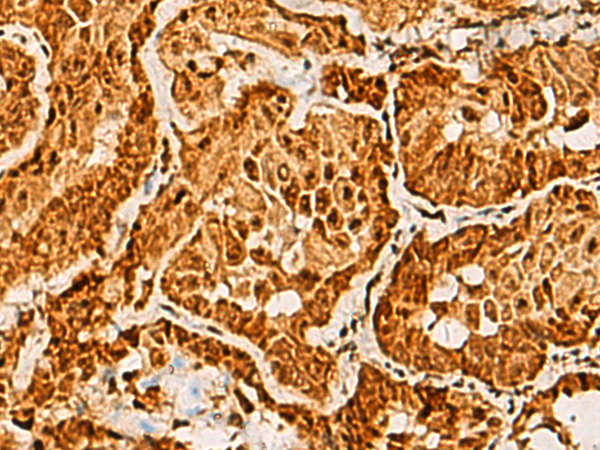

分类: 科研抗体货号: P10359别名: GODZ; DHHC3; DHHC-3; ZNF373应用: IHC反应种属: Human, Mouse